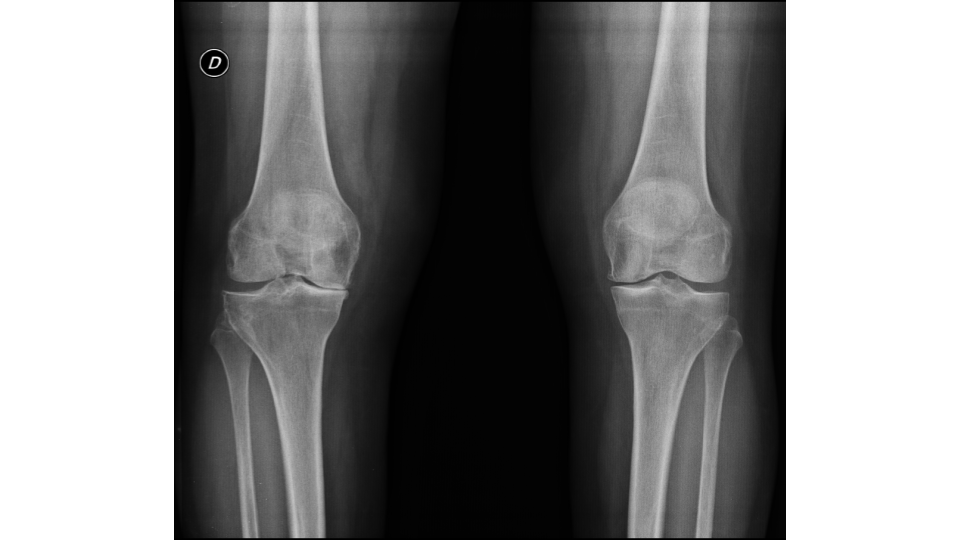

Se analizó un total de 36 prótesis en 32 pacientes. De este total, 25 (78 %) fueron de sexo femenino y 7 (22 %), de sexo masculino. Cuatro pacientes presentaron reemplazo bilateral (Figs. 1, 2 y 3).

Figura 1. Radiografía anteroposterior de ambas rodillas que muestra genu valgo bilateral secundario a artrosis.